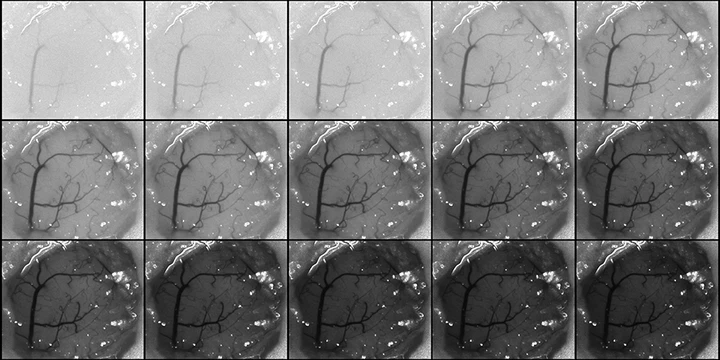

Speckle contrast images acquired at different exposuresMulti-exposure speckle imaging (MESI) is an advanced form of laser speckle contrast imaging that offers more robust estimates of flow across a wider range of flow speeds. By revisiting the underlying physics behind LSCI to better account for the presence of static scatterers and capturing imagery at multiple exposure times, MESI enables the chronic tracking of cerebral blood flow. These improvements have allowed us to study the hemodynamics of ischemic stroke across timescales spanning seconds to months after the infarct.